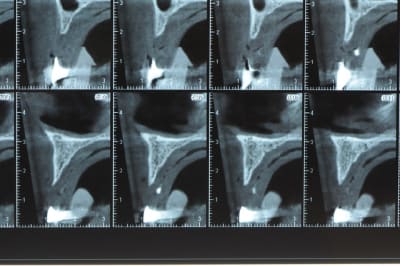

un cas pour PXAV.

ça c'est le domaine de pxav.

qu'en penses tu ?

j'ai besoin de 4 implants au maxillaire pour faire tenir son complet.

dans la zone postérieur, pas de problème, mais devant, c'est une autre histoire.

Non sans décorner, superbe cas de début pour expansion, bone splitting et tout et tout.

la corticale a l'air tiptop, par contre en cas d'expansion il faut eventuellemnt augmenter le nombre d'implant à 6 pour compenser eventuellement le manque d'epaisseur 'avis personnel)

Je suis sceptique sur la gestion de ce cas par bone splitting puisqu'il met parait très difficile d'obtenir un volume osseux peri-implantaire crestal suffisant et satisfaisant.

+1 Olive, ce serait à mon avis plus prédictible avec des greffes. Je doute qu'on puisse obtenir suffisamment d'os en vestibulaire et en palatin des implants en splittant une crête aussi fine.

De ce que j’ai vu du cas de D57 c’est me semble t il un magnifique cas d’expansion, ce qui ne veut pas dire rien d’autre

Ce n'est pas vraiment un consensus mais plutot du bon sens. Si tu as une crête en profil de lame de couteau cela signifie que tu as une fusion des corticales vestibulaire et palatine et donc absence de spongieux, ce qui comme tu le sais n'est pas indiqué en implanto (cj os de marbre par exemple)

Il me semble que Palti ou encore Szmukler-Moncler recommandent un minimum de 2-3mm. Si c'est plus fin, greffe d'apposition et GBR.

Dans ton cas il te faudrait abaisser la crête de 3 bons mm pour arriver à cette épaisseur.

Une petite étude de ton cas D57

Sous réserves bien sur de voir l’animal en vrai

Les zones exploitables radiologiquement parlant:

Coupes implant

2,3 40100

4,96 35130 avec sinus lift mais difficile

5,25 35150

6,02 35130

6,78 35115 après réduction de hauteur de crête

7,26 35115 après réduction de hauteur de crête

8,51 35150

10,43 40115 ou 50115

11,10 40115

Ce qui nous fait 9 implants possible évidement avec un comblement de sinus on augmenterait encore les zones implantable mais ce n’est pas le but recherché, avec 8 (4+4) il doit être possible de faire une belle barre support de complet